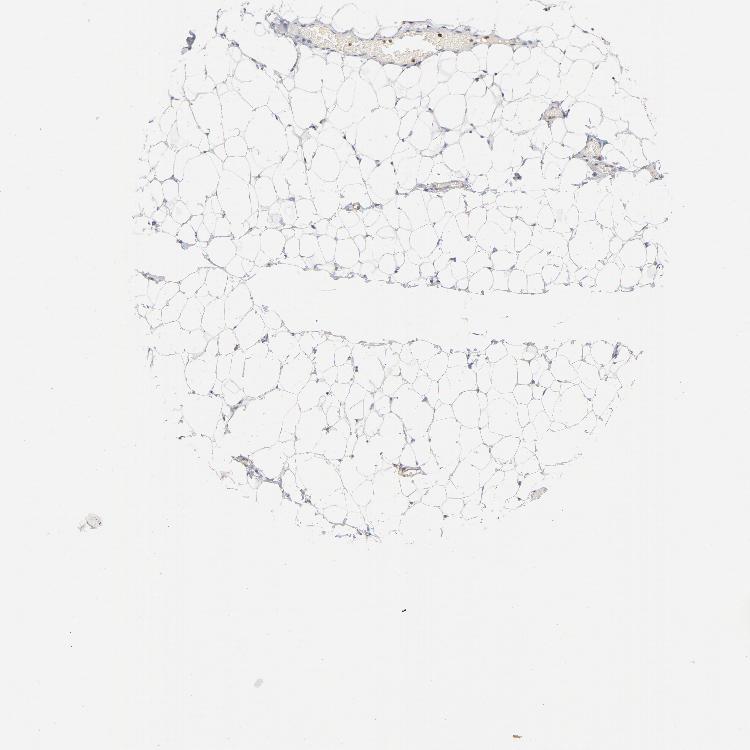

TISSUE PRIMARY DATA SOFT TISSUE Show tissue menu

SOFT TISSUE - Expression summary

SOFT TISSUE 1 - Antibody stainingi

Antibody staining in the annotated cell types in the current human tissue is reported as not detected, low, medium, or high, based on conventional immunohistochemistry profiling in selected tissues. This score is based on the combination of the staining intensity and fraction of stained cells.

Each image is clickable and will lead to virtual microscopy that enables deeper exploration of all samples and also displays staining intensity scores, fraction scores and subcellular localization as well as patient and tissue information for each sample.

Antibody HPA021616Antibody CAB004035Antibody CAB075739

Chondrocytes Not detected-Not detected

Fibroblasts Not detectedNot detectedNot detected

Peripheral nerve Not detectedMedium-